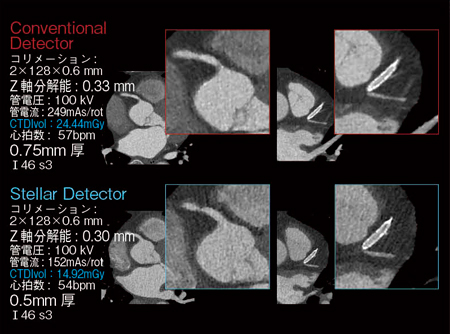

従来,0.33mmだったZ軸方向の分解能は,Stellar DetectorのEdge technologyによって0.3mmに向上した。0.75mm厚(カーネルⅠ46)で再構成した画像の冠動脈を拡大して見ると,Stellar Detectorでは非常にシャープになっている。

Edge technologyにより,最小再構成厚は0.5mmまで向上した。0.75mm厚と比較すると,ノイズが目立つようになるものの,冠動脈CTとしては十分な,分解能の高い画像が得られる(図3)。

図3 冠動脈CTAにおけるConventional DetectorとStellar Detectorの比較

われわれも,従来は0.75mm厚を基本としていたが,Stellar Detectorへのアップグレード後,通常の冠動脈CTでは0.6mm厚で再構成し,ステント留置例などでは0.5mm厚を用いている。0.5mm厚で再構成することによって,ステントの構造がはっきりと見えるようになり,内腔も格段に評価しやすくなっている(図4)。